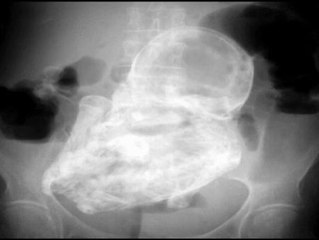

Una mujer brasileña con un feto calcificado desde hace 30 años muere en una operación